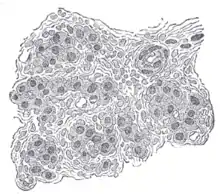

Le corpuscule carotidien ou glomus carotidien[1],[2],[3] est un petit groupe de cellules chimioréceptrices et supportant les cellules sustentaculaires[4],[5].

Ce glomus est situé dans l'adventice en arrière de la carotide au niveau de sa bifurcation à la hauteur de la quatrième vertèbre cervicale.